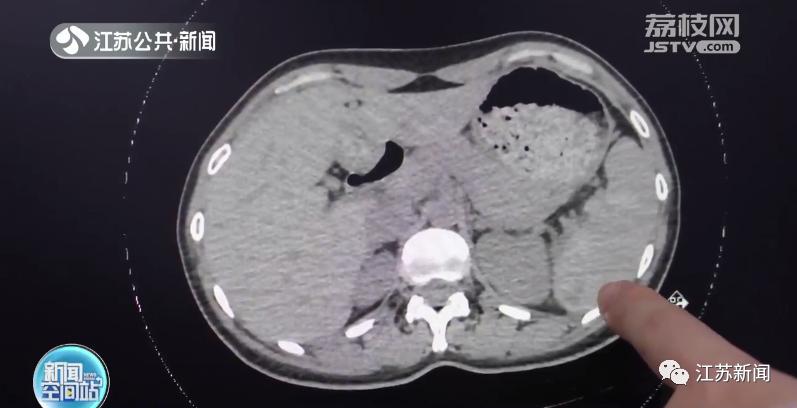

常州市第七人民醫(yī)院胸心外科副主任醫(yī)師俞文俊介紹:“查了CT,發(fā)現(xiàn)了劉女士脾臟有出血、腹腔有積液,考慮是脾破裂。但她這個(gè)脾破裂跟平時(shí)急性的破裂不一樣,她是遲發(fā)性的脾破裂!

圖片

醫(yī)生介紹,摔倒導(dǎo)致遲發(fā)性脾破裂其實(shí)比較常見。脾臟出現(xiàn)小的損傷后,伴有持續(xù)性的出血,當(dāng)出血量超過脾臟包膜的壓力時(shí)就會發(fā)生破裂,造成腹腔內(nèi)出血,嚴(yán)重時(shí)可能危及生命。